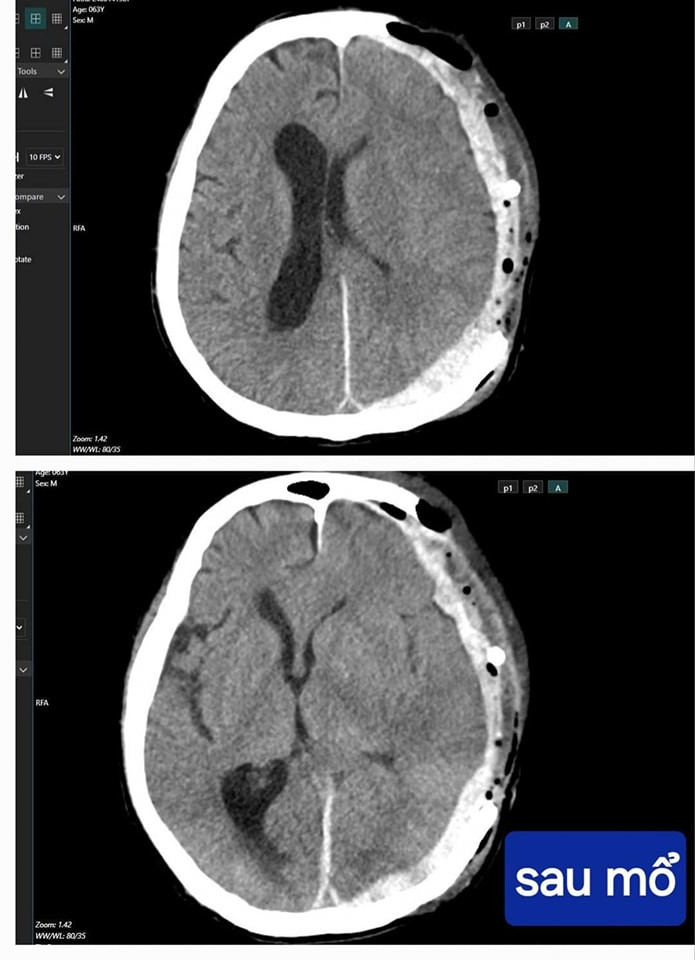

![]() |

| Bệnh nhân hồi phục sau phẫu thuật - Ảnh BVCC |

Bằng sự tận tâm cứu chữa người bệnh của đội ngũ y bác sĩ Bệnh viện Hữu nghị Việt Nam - Cu Ba Đồng Hới cùng sự may mắn của bệnh nhân, sau mổ, người bệnh phục hồi rất tốt và đã được ra viện sau 10 ngày điều trị.

Lúc xuất viện, bệnh nhân trong tình trạng tỉnh táo, không yếu liệt. Đây là một niềm vui to lớn đối với đội ngũ y bác sĩ Bệnh viện và của cả gia đình bệnh nhân.